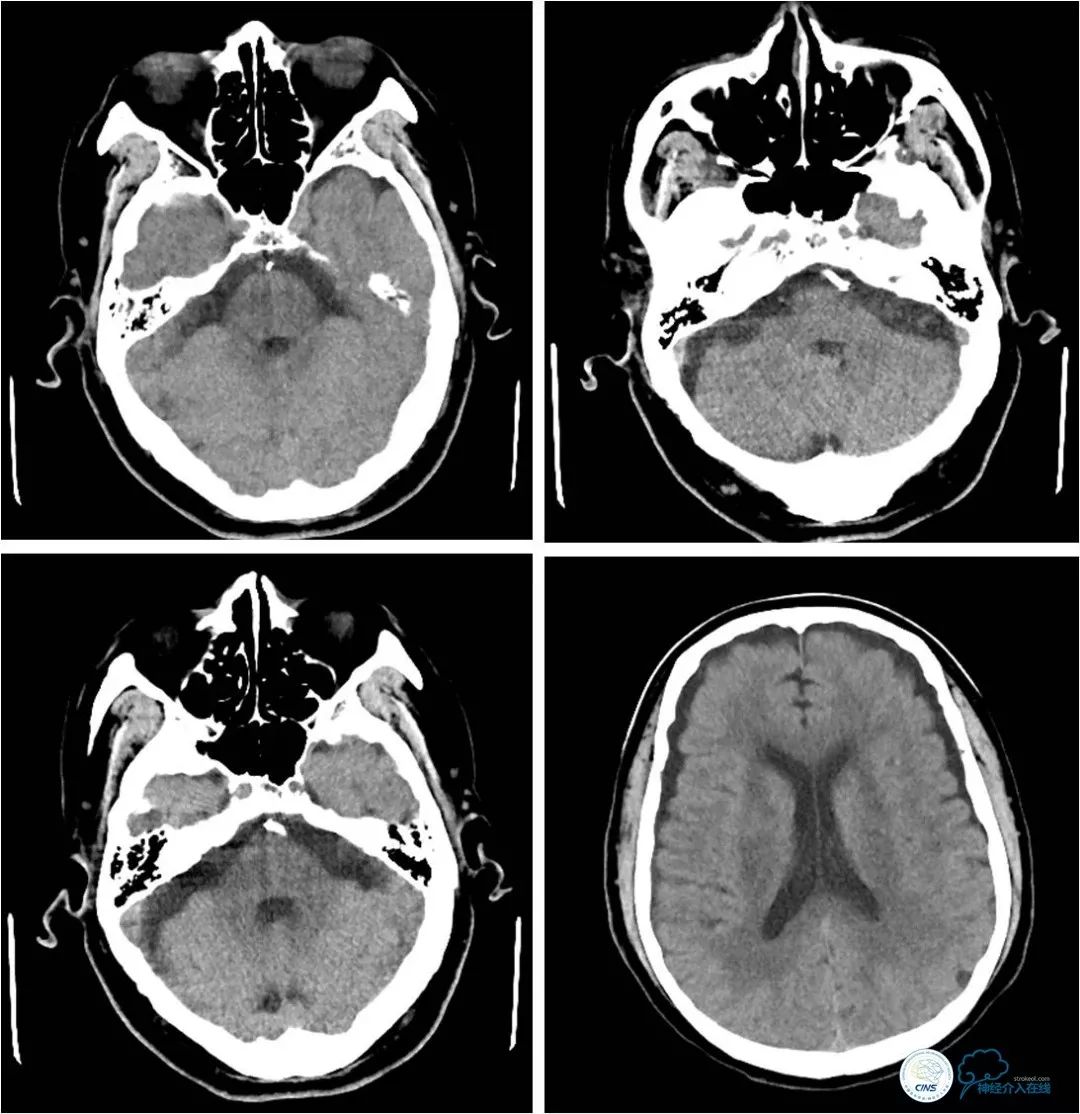

患者,男,72岁。主因“反复头晕3年”入院。患者3年前突发短暂头晕,无其他伴随症状,就诊于当地医院,行CTA提示:双椎动脉V4段-基底动脉交界区狭窄。3年来症状反复发作,多次行颅内动脉血管成像,显示病变程度逐渐加重(图1)。

图1

头部CTA:双椎动脉-基底动脉交界区重度狭窄(图3)。

图3